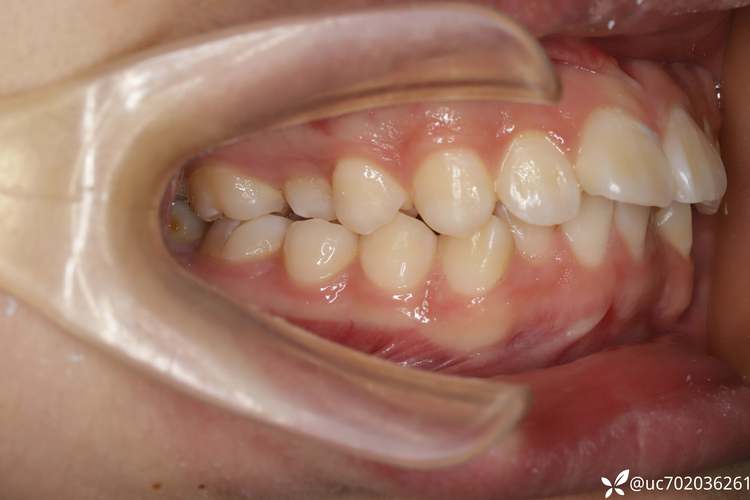

- 这是专业决策: 拔除磨牙是正畸医生基于对你口腔全面检查(包括模型、X光片、口内照片、面型分析等)后做出的专业治疗计划的一部分,医生认为拔除这颗磨牙是解决你牙齿问题的最佳或必要方案。